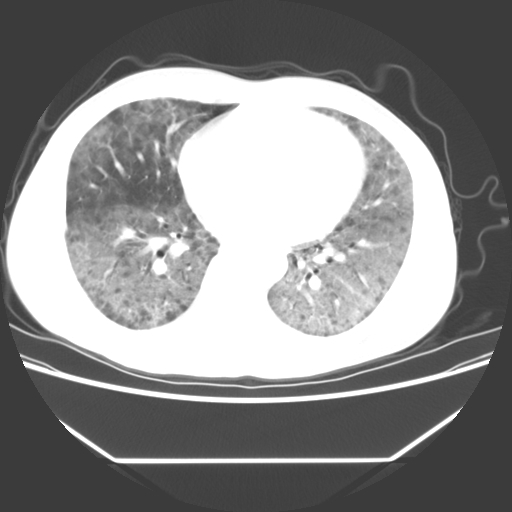

病人55岁,咳嗽,胸闷

忘了传病史了,病人55岁,咳嗽,胸闷

两肺部呈“毛玻璃”状改变,原因待查考虑感染性病变

病人是否发烧,两肺“磨玻璃”影,其间见空气支气管征和碎路石征。考虑肺泡蛋白沉着症。

两肺广泛对称磨玻璃样影,密度不均,考虑机遇性肺部感染。

双肺弥漫磨玻璃样病变,病史很重要。有感冒或发烧史,甲流不除外。无发烧可考虑肺泡蛋白沉积,但肺泡蛋白沉积边缘往往较清晰,与正常肺组织分界清晰

两肺弥漫间质性病变,考虑肺泡蛋白沉着症。建议进一步检查。

此病人我并没有见到,病史没有得到更详细,但此病人据说有发低热,请教各位老师,此病人像不像卡氏肺囊虫肺炎

考虑pcp?不像肺泡蛋白沉着症。